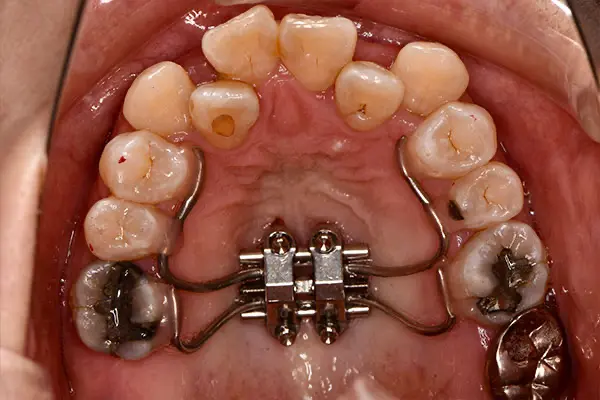

叢生・反対咬合

術前正面

術中正面

術後正面

術前上顎

| 主訴 | 歯のでこぼこ |

|---|---|

| 診断名あるいは主な症状 | 叢生、反対咬合 |

| 初診年齢 | 45歳 |

| 治療内容・装置 | マルチブラケット装置(上下表側からの矯正治療) MSE2 |

| 抜歯・非抜歯 | 下顎左第二小臼歯抜歯 |

| 治療期間 | 2年9ヶ月 |

| 費用 | 882,700円(税込) |

| 治療のリスク・副作用 | 歯の移動に伴う痛み 上下顎前歯部の歯根吸収 装置による口内炎 ブラッシング不良によるむし歯、歯周炎 |